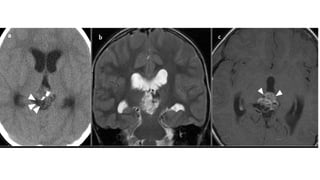

CT Findings

• Relatively large tumours

• Slight hyperdense (high cellular tumor)

• Classically, shows or "exploded" similar to pineocytomas ( In contrast,

pineal germinomas tend to engulf pineal calcification)

MRI Findings

• Irregular masses often with evidence of invasion into the adjacent

brain

• T1: Isointense to hypointense to adjacent brain

• T2

• Isointense to adjacent brain

• areas of cyst formation or necrosis may be present

• T1 C+ (Gd): vivid heterogeneous enhancement

• DWI/ADC- restricted diffusion due to dense cellular packing

• Central cystic necrosis is sometimes present and thus can

roughly mimic a pineal cyst, although the latter should have

a smooth, thin wall

• Screening of the whole neural axis is necessary as CSF seeding is seen

in 45% of cases.

• #30 highest grade tumour among pineal parenchymal tumours and are considered WHO grade 4 tumours (M:F 0.7:1; similar to other pineal parenchymal tumours), which is in contrast to the male predominance seen in pineal germinomas)

• #31 Trilateral retinoblastoma refers to the combination of retinoblastoma (usually bilateral) and pineoblastoma. This association highlights the close relationship between these highly aggressive small round blue cell tumors. Approximately 5-15% .

• #35 A large mass ( * ) centered on the pineal region elvates, splays and partially engulfs the internal cerebral veins (blue arrows). Pineal calcifications (red arrows) are best seen on CT and are located at the periphery of the mass.  Enhancing soft tissue is also seen filling the floor of the third ventricle (green arrows) and in the lateral ventricles (best seen in the left forntal horn - yellow arrow).

• #36  the pineal region shows a lobulated soft tissue mass lesion, it measures about 2.9 X 2.7 X 2.7 cm in its main diameters  the lesion shows mildly hypointense T1 and hyperintense T2 / FLAIR signal, with inhomogenous post-contrast enhancement the lesion shows mild restricted diffusion a suspected small signal void focus is seen at its peripheral anterior aspect of the lesion (which was evident on CT study that was available with the patient)  the lesion is seen compressing the superior portion of the cerebral aqueduct with moderate supratentorial hydrocephalus as well as transependymal CSF permeation mild downward herniation of the cerebellar tonsils is noted